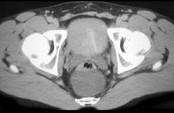

问题 男,21岁,下腹部一囊性肿块,无压痛,请结合图像,选择最可能诊断 ( )

选项 A.盆腔脓肿 B.结肠重复畸形囊肿 C.神经纤维瘤 D.神经鞘瘤 E.间质瘤

答案 B